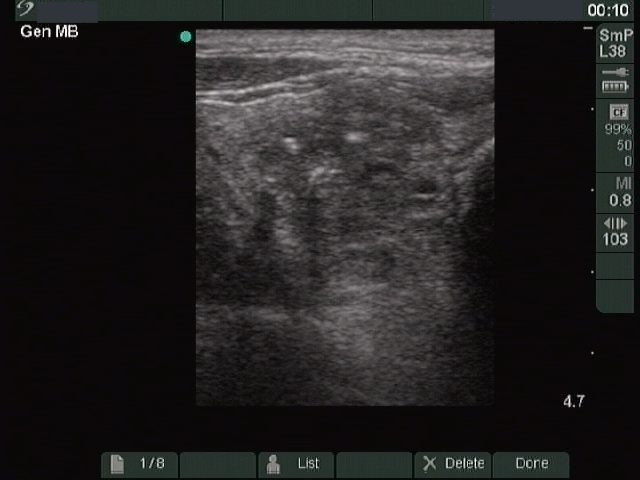

Ultrasonography: a hypoechogenic nodule with dimensions 29x24x33 mm. The nodule presented neither halo sign, nor perinodular blood flow.